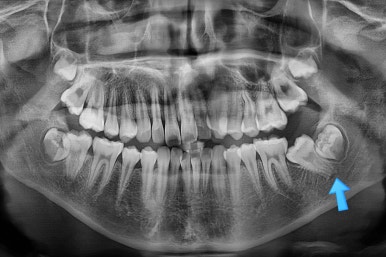

X-ray를 보면 사랑니가 어부바 하고 있어서 나와야 될 어금니가 짓눌려 있는 양상이었어요.

이 경우 방향을 잘못잡아서 바로 앞 어금니도 밀어버리거나 해를 가할 수 있는 상황이었습니다.

사랑니가 잘못 나는 바람에 사랑니 포함 치아 3개가 문제될 수 있는 상황이었어요.